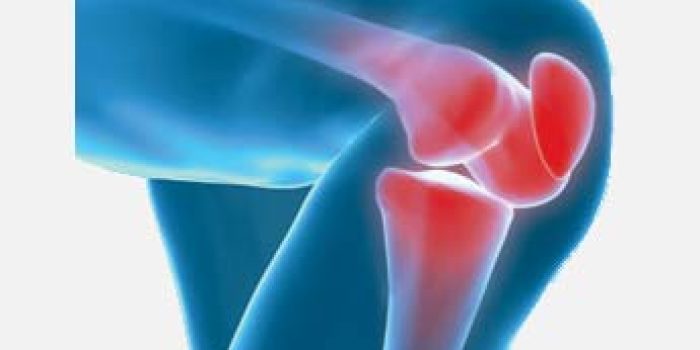

بسیاری از مردم در سنین مختلف از درد زانو رنج میبرند.زانو درد یکی از شایعترین مشکلات عضلانی اسکلتی است که علل متعددی در ایجاد آن دخالت دارند و این روزها باعث مراجعه تعداد زیادی از افراد به پزشک میشود.

راه هایی برای تسکین درد زانو

این توصیهها به تسکین درد جزئی زانو کمک می کنند